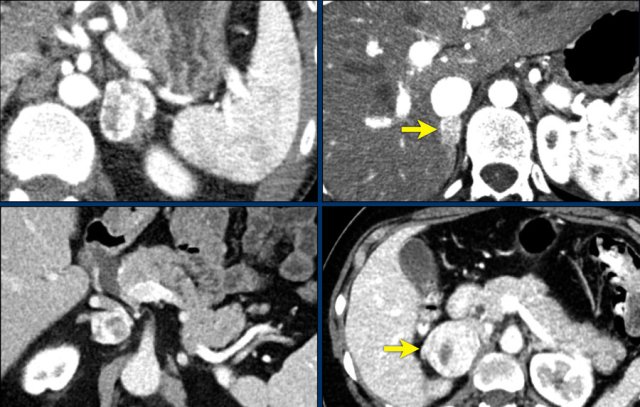

The axial venous phase CT on the left shows a large inhomogeneously enhancing right adrenal lesion with a small cyst, which could not be diagnosed as an adenoma with CT washout, making it an indeterminate lesion.

The plasma free metanephrines were elevated and the lesion was diagnosed as a pheochromocytoma.

MIBG SPECT for staging showed intense uptake in only the right adrenal gland.

PET-CT was also performed, which in contrast showed uptake only slightly higher than normal liver.

This is highly unusual for pheochromocytomas, which are usually very FDG-avid, even when they are benign.

If the primary tumor lacks FDG uptake, the sensitivity for finding metastases on an FDG PET-CT will be very low.